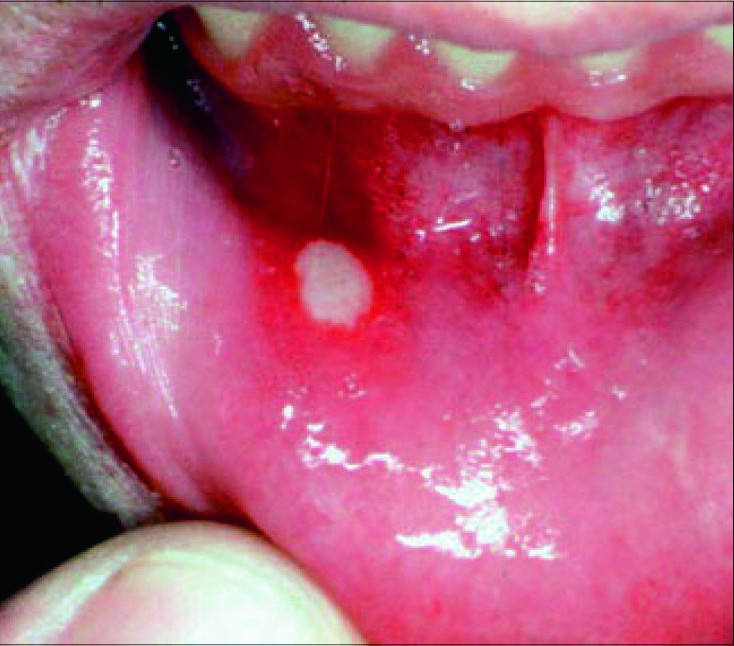

Suulimaskesta haavandiline põletik ehk aftoosne stomatiit on väiksemate või suuremate valulike haavandite ehk aftidega (sügav limaskesta defekt) kulgev suuõõnehaigus. Sagedamini on tegemist erosioonidega (pindmine limaskesta defekt). Taastuva haavandilise stomatiidi all kannatab umbes 10% elanikkonnast. Haigust esineb naistel rohkem kui meestel, lastel ja vanuritel tuleb seda ette harva.

Ravi on sümptomitest lähtuv. Kõigepealt peab vaigistama valu (paikne tuimastus nt 2%-lise lidokaiiniga; kootavatest vahenditest nt fenoolkamper ja 7%-line tanniin). Haavandi kiiremat paranemist soodustavad paikselt kasutatavad glükokortikosteroidgeelid, haavandivaba perioodi aitavad pikendada süsteemsed kortikosteroidravimid.